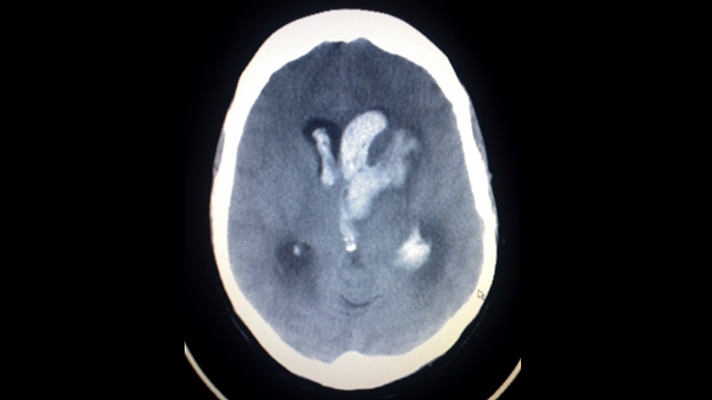

IBM Watson Health and Israel-based MedyMatch Technology are joining their AI forces in hospital emergency rooms to help doctors detect intracranial bleeding resulting from head trauma and stroke. The MedyMatch algorithm uses deep learning, machine vision, patient data and clinical insights to automatically highlight for a physician areas that might indicate the potential presence of cerebral bleeds.